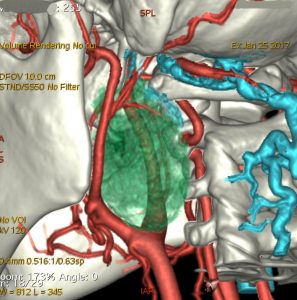

症例:頸静脈孔より下の深頸部のもの:副咽頭間隙腫瘍

左頸静脈孔の下の迷走神経節から発生したものです。ごく軽い飲み込み辛さだけが症状でした。

内頚動脈を強く圧排して,外形動脈からはかなり豊富な血流が流入しています。頭頸部外科で顎骨を割るような手術を計画されていました。

でも,右側の画像で見るような角度から,小さな頸部の皮膚切開だけで,胸鎖乳突筋だけを乳様突起から外して翻展して摘出できました。内部からほじくるように摘出すれば症状悪化はないのですが,周囲軟部組織から切断して剥離しようとすると厳しい嚥下障害と嗄声になります。

手術で全摘出しましたが嚥下障害などはでませんでした。普通のおとなしい神経鞘腫ですから再発はありません。